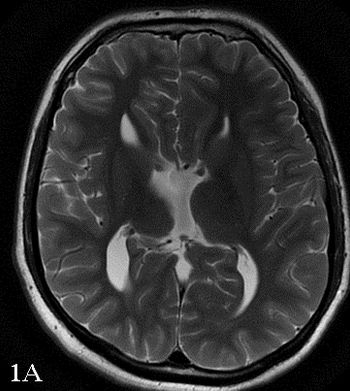

48-year-old female presented with complaint of seizures.